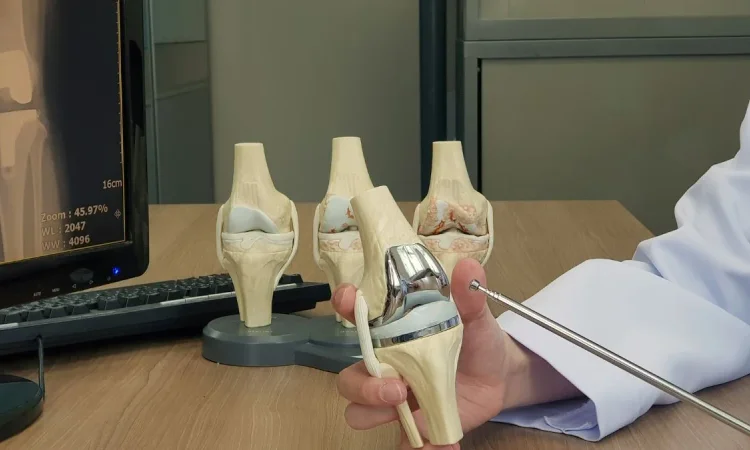

The precision required in knee replacement surgery is immense, as even minor errors in implant positioning can lead to premature wear or joint instability. Traditionally, surgeons relied on experience and manual guides, but data analytics integrated with robotic-assisted surgery systems is revolutionizing this process.

Robotic platforms collect real-time intraoperative data, including three-dimensional mapping of the joint and bone structure. Analytics algorithms process this data to guide surgeons in placing implants with optimal alignment and fit. This level of accuracy is unattainable through manual methods alone and has been linked to improved long-term joint function and reduced revision surgeries.

Additionally, advances in 3D printing allow for the creation of patient-specific implants informed by detailed data models. This level of customization improves implant integration and longevity.